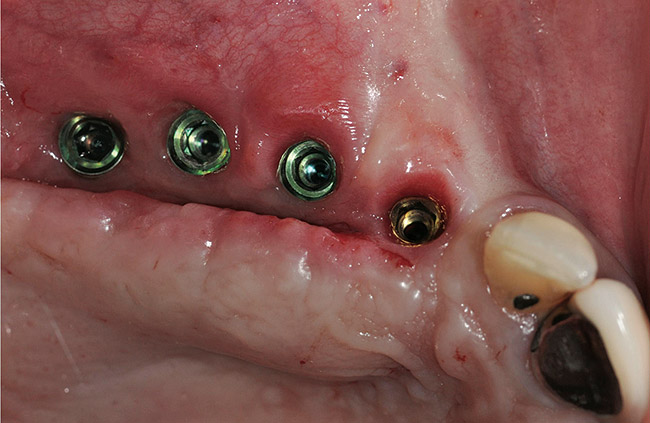

A 72-year-old man was referred for removal of failing maxillary right posterior implants (Figure 19). The treatment plan included removal of three implants with simultaneous bone augmentation and replacement implants for implant-supported fixed bridgework. Implant removal and bone grafting with rhPDGF (Gem 21®, Osteohealth, www.osteohealth.com) and allograft (MinerOss) and xenograft (BioOss®, Geistlick, www.geistlickonline.com) were used along with titanium mesh for space maintenance (Figure 20, Figure 21 and Figure 22). Six months later, mesh removal revealed type I bone allowing for placement of three implants (Figure 23 and Figure 24).

Figure 23  Trephinated core biopsy obtained at 5 months.

Figure 23

Figure 24  Histology: Note active osteocytes with new bone formation.

Figure 24